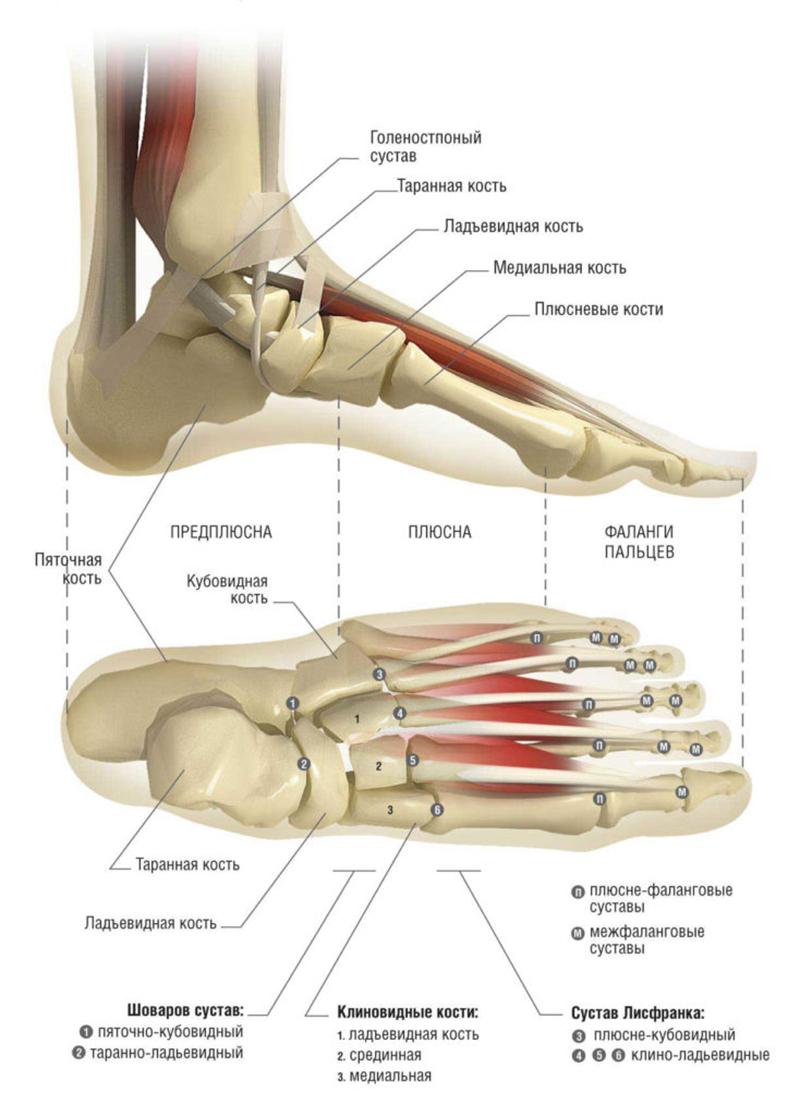

Кости голеностопа

Голеностопный сустав состоит из двух основных костей: малоберцовой и большеберцовой. К ним снизу присоединяется таранная кость, а под ней располагается пяточная кость. В результате образуется структура, напоминающая блок, которая является характерной формой голеностопного сустава. В этой конструкции выделяются ключевые элементы: наружная (внешняя) и внутренняя лодыжки, а также дистальная часть большеберцовой кости.

Каждая из этих анатомических структур имеет участки для крепления связок и фасций, а также углубления, через которые проходят кровеносные сосуды. Изображения с пояснениями костей предоставляют наиболее полное представление о дополнительных образованиях, находящихся на них.

Голеностопный сустав находится на стыке малой и большой берцовых костей с пяточной костью, которая является частью стопы. Существует четыре области голеностопа: задняя, передняя, наружная и внутренняя. Последние две расположены в области лодыжек. Передняя часть представляет собой тыл стопы, а задняя – область ахиллова сухожилия.

Что касается внешней границы голеностопного сустава, то условная линия, обозначающая его наружную часть, проходит примерно на 8 см выше лодыжек как с внешней, так и с внутренней стороны. Прямая, соединяющая эти выступы, служит границей между суставом и стопой.